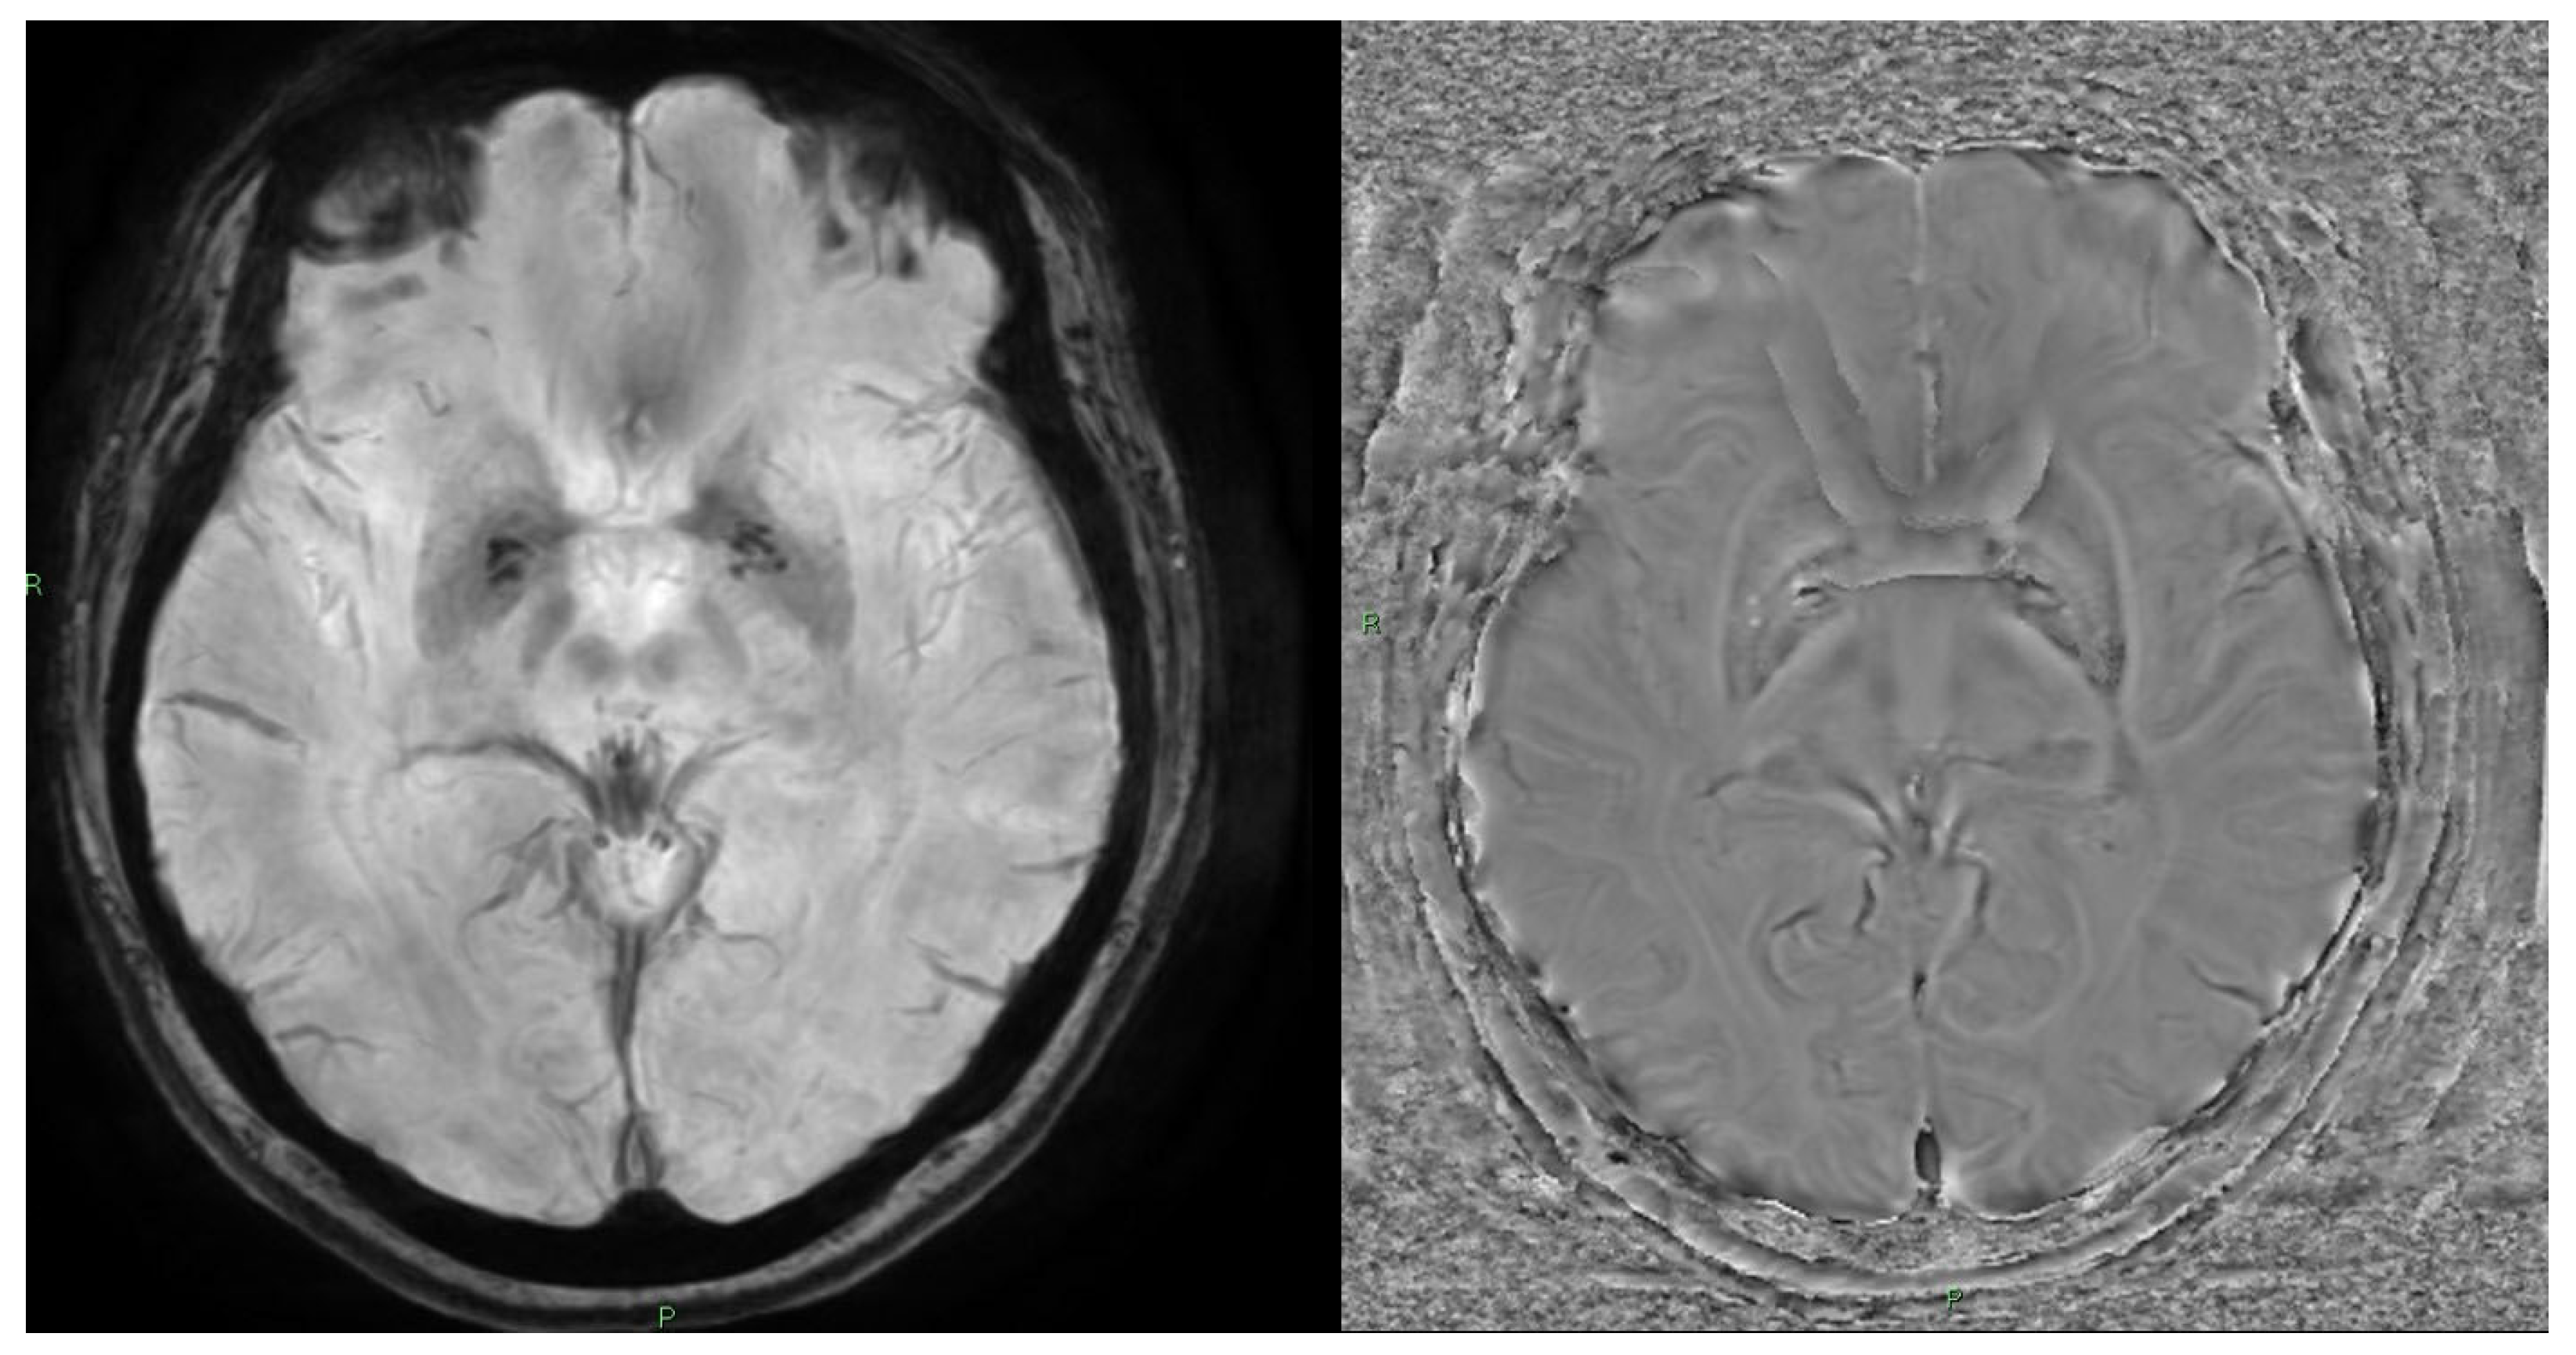

10. Quantitative Susceptibility Mapping (QSM) and Susceptibility-Weighted Imaging (SWI)

10.1. Physics and Signal Model

10.4. Clinical Applications

- Liu, C.; Li, W.; Tong, K.A.; Yeom, K.W.; Kuzminski, S. Susceptibility-weighted imaging and quantitative susceptibility mapping in the brain. J. Magn. Reson. Imaging 2014, 42, 23–41. [Google Scholar] [CrossRef]

- Liu, S.; Buch, S.; Chen, Y.; Choi, H.; Dai, Y.; Habib, C.; Hu, J.; Jung, J.; Luo, Y.; Utriainen, D.; et al. Susceptibility-weighted imaging: Current status and future directions. NMR Biomed. 2016, 30. [Google Scholar] [CrossRef]